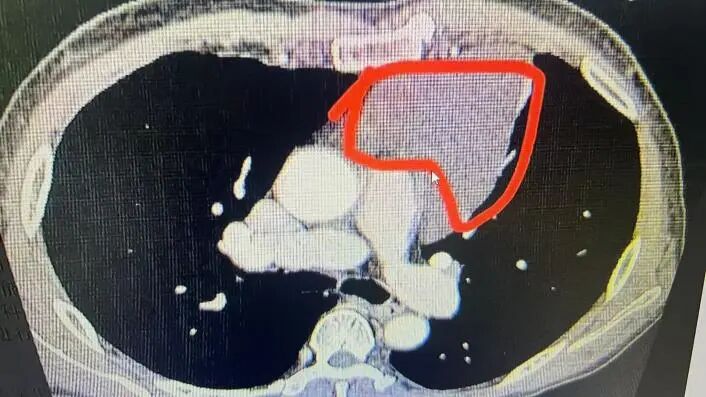

半个月前,患者李先生(化名)突发晕厥,被紧急送往潜江市中心医院胸外科就诊。经胸部CT检查发现,其前纵隔区域长有巨大肿瘤,医生诊断为前纵隔囊肿。该肿瘤紧邻心脏大血管,万幸的是,肿瘤与周边重要组织间尚存可操作间隙,为手术切除留下了希望。